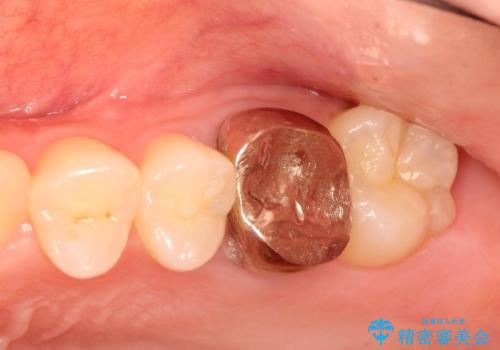

金属の奥歯 → 白い奥歯 根管治療からのやり直し

- 再根管治療→土台の築造 を行った上でのかぶせ物のやり替えをおこないました。

神経の無い歯のかぶせ物をやり替える際は、是非根管治療からしっかりやり直すことをおすすめします。

かぶせ物の種類:Bellezza